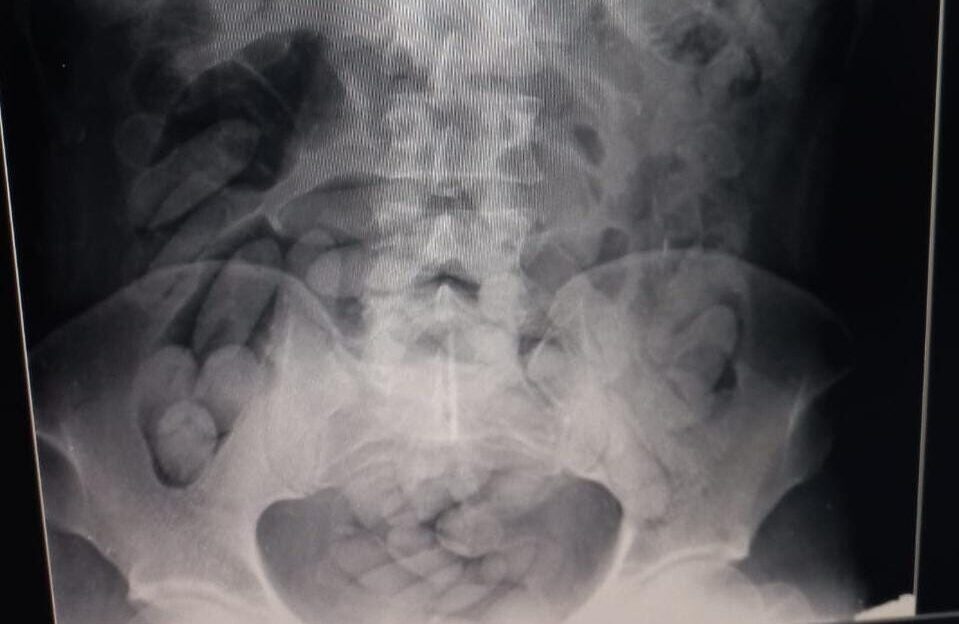

Radiografia do corpo do homem preso (Foto: Divulgação/PMRv)

Um casal de estrangeiros acabou preso na manhã desta quarta-feira (2) após ser flagrado com drogas no estômago, em uma ação da Polícia Militar Rodoviária na rodovia Rachid Rayes (SP-333), em Marília. Patrulheiros abordaram o coletivo que fazia o itinerário entre Campo Grande (MS) e Belo Horizonte (MG).

Durante fiscalização, os militares notaram que um casal apresentou desconforto com a presença das equipes. Em conversa com os policiais, eles informaram que eram bolivianos e confessaram que tinham ingerido cocaína em cápsulas em Puerto Quijarro, na Bolívia.

Os bolivianos foram encaminhados para o Hospital de Clínicas (HC) de Marília, para exames de imagem e retirada das cápsulas.